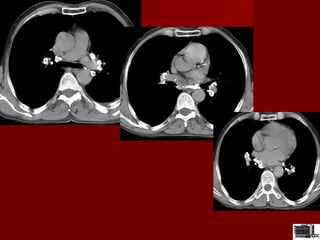

Chist pleuro-pericardicChist pleuro-pericardic

Formatiune cu sediul in mediastinul anterior etaj inferior ,unghiul

cardio-frenic omogena,contur net

•Chist pleuro-pericardicChist pleuro-pericardic

CT –chistul pleuro pericardic se

localizeaza cel mai frecvent in

unghiul cardiofrenic drept

este o structura chistica cu o

densitate de –5-25 UH

peretele este fin

dupa admininstrarea substantei

de contrast nu-si modifica

densitatea

Chist pericardicChist pericardic

•masa in unghiul

cardiofrenic anterior

•densitate lichidiana